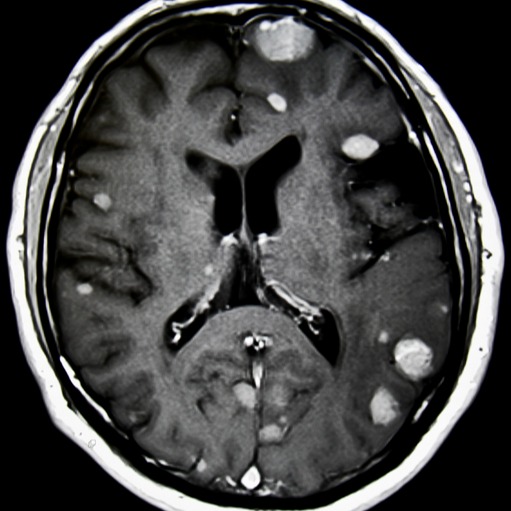

Metastasi cerebrali

La diagnosi della presenza delle metastasi cerebrali si ottiene grazie ad indagini diagnostiche avanzate come la TAC o, ancor di più, con la Risonanza Magnetica, che offre migliore risoluzione per lo studio del cervello, spesso a seguito di una diagnosi già nota di neoplasia di altri organi.